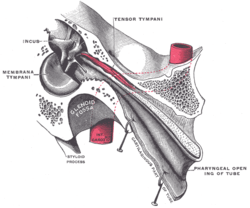

Auditory tube, laid open by a cut in its long axis. | |

External and middle ear, opened from the front. Right side. Chain of ossicles and their ligaments, seen from the front in a vertical, transverse section of the tympanum.

Chain of ossicles and their ligaments, seen from the front in a vertical, transverse section of the tympanum. Ossicles

Ossicles Tympanic cavity. Facial canal. Internal carotid artery.

Tympanic cavity. Facial canal. Internal carotid artery.- Auditory ossicles. Tympanic cavity. Deep dissection.